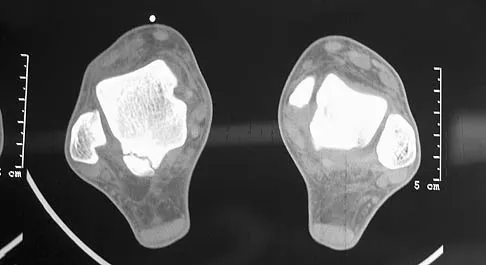

Question 98

A 50-year-old laborer sustained an isolated closed injury to his heel after falling 11 feet off a wall. A radiograph and a CT scan are shown in Figures 4a and 4b. To minimize the patient's temporary disability and allow him to return to work most rapidly, management should consist of

Explanation